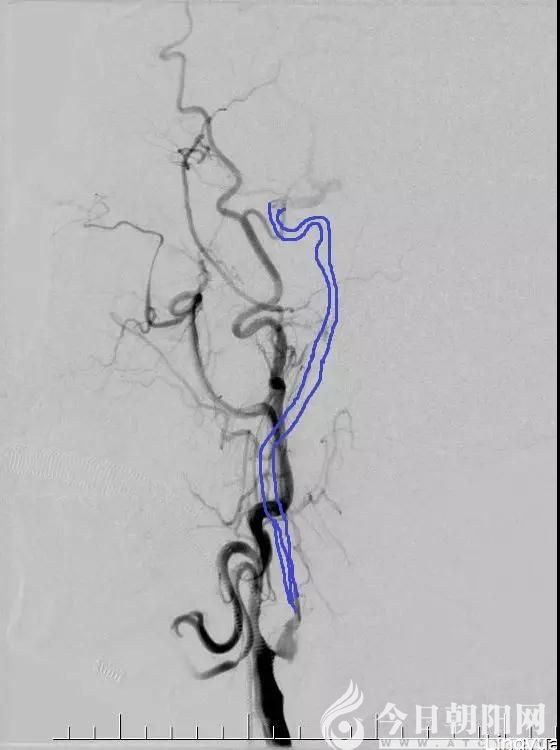

手術(shù)中發(fā)現(xiàn),患者的病變部位遠(yuǎn)比預(yù)想的病情要復(fù)雜得多,右側(cè)鎖骨下動脈近端閉塞、右側(cè)椎動脈閉塞、右側(cè)頸總動脈近端重度狹窄90%、右側(cè)頸內(nèi)動脈起始段已經(jīng)完全閉塞、遠(yuǎn)端的血管已經(jīng)完全不顯示。全腦血管造影后,前交通動脈也是不通的,這意味著患者的對側(cè)頸內(nèi)動脈對患側(cè)完全沒有代償,情況非常危急。經(jīng)家屬知情同意后,進(jìn)行了2次支架取栓,患者頸內(nèi)動脈起始段終于獲得了部分開通。

術(shù)前顯示頸內(nèi)動脈起始段閉塞,藍(lán)筆所標(biāo)識部位為正常頸內(nèi)動脈的走行情況。